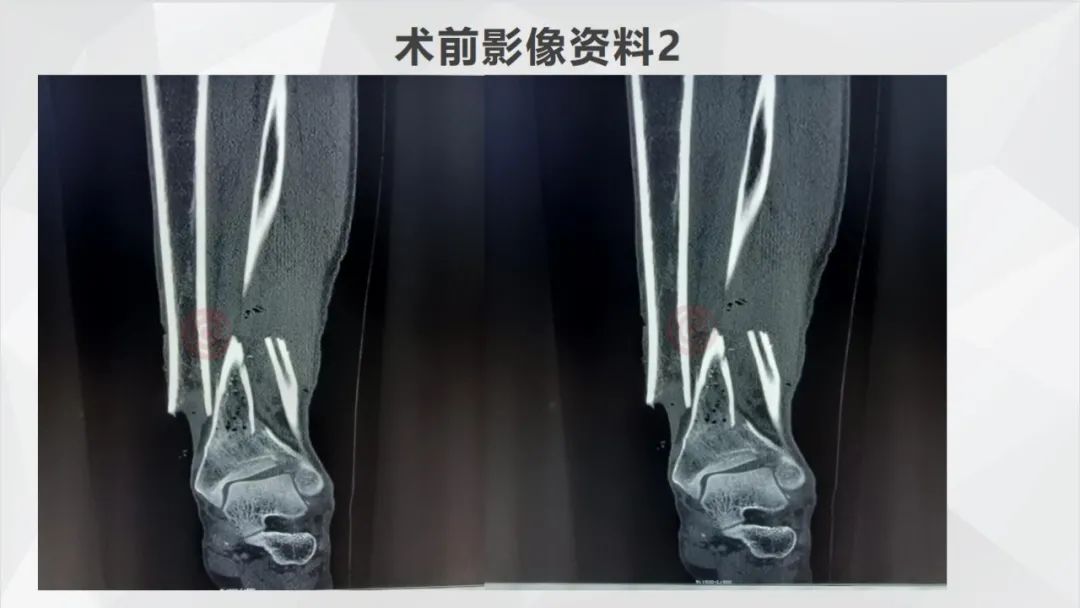

辅助检查:胸部CT、右胫腓骨+右踝部CT重建示右侧胫腓骨下段粉碎性骨折伴周围软组织挫裂伤,胸部CT平扫未见明显异常。右胫腓骨+右踝关节DR示右侧胫腓骨下段粉碎性骨折并局部软组织挫裂伤,右腓骨头骨折。心电图未见明显异常。

640 (32).jpg

▲患者术前影像